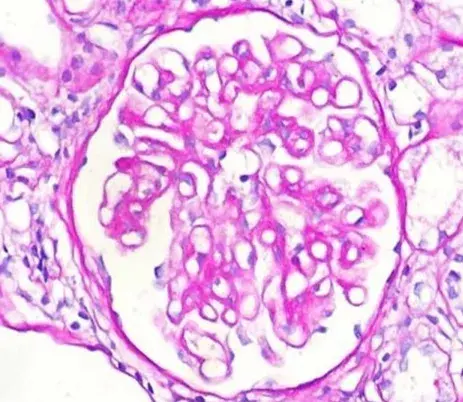

La inmunofluorescencia muestra marcação linear de IgG en la MBG (anticuerpo anti-IgG; 400×).

La inmunofluorescencia demostró un patrón de deposición lineal de IgG (policlonal), con deposición en la membrana basal glomerular (MBG), sin depósitos en la microscopía electrónica.